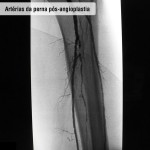

Doença obstrutiva em diabéticos